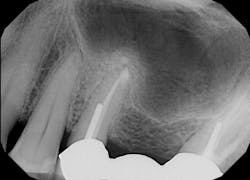

Continuing to adjust spot size, mist, and power as necessary, the laser was used to enlarge the fenestration in the buccal plate (figure 4). The granulation tissue from the abscess then had to be removed in order to expose the root for amputation. Simultaneously, a slot prep was cut for retrograde bioceramic restoration (figure 5).

After using a round burnisher and blow test to determine that there was no perforation to the sinus and the membrane was still intact, the laser was used at a spot size of 1.25 mm, on low power mode, and without mist or air to debride the medial superior area of the bony defect. X-rays were taken following immediate placement of bone-graft material to display the site after using Solea to remove bone and granulation tissue (figures 6 and 7). The entire procedure, including the bone graft, took approximately 40 minutes from start to finish.